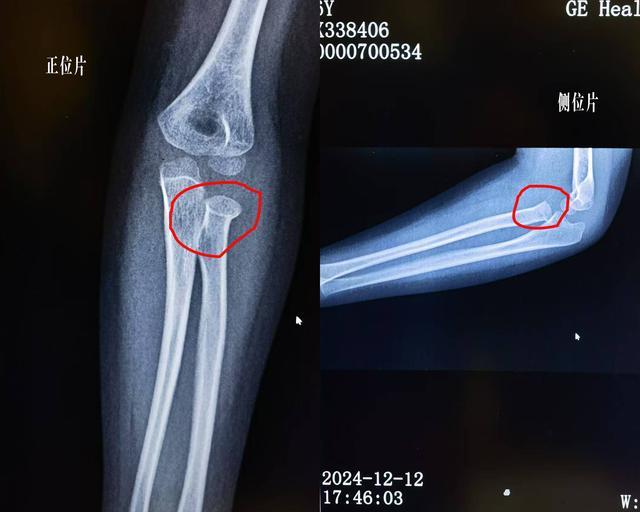

事件原委还得从12月12日说起,家住衡阳市6岁的蒋瑞晨(化名)因左桡骨小头骨折(歪戴帽)来常宁市中医医院骨伤二科就诊。

▲手法复位前在衡阳某三级医院拍的X光

▲经南詹正骨手法复位后复查影像

神奇的一幕也就在这一刻发生了,在确诊为左桡骨小头骨折后,尹书东运用南詹正骨专长绝技,结合折顶回旋、拔腕屈肘等复位手法,前后也就短短一分钟左右就成功整复骨折。因为骨折复位得太完美,超出人们的想象,在随后的拍片复查中,X光片上看不出骨折线检查报告为“未见骨折脱位征象”。